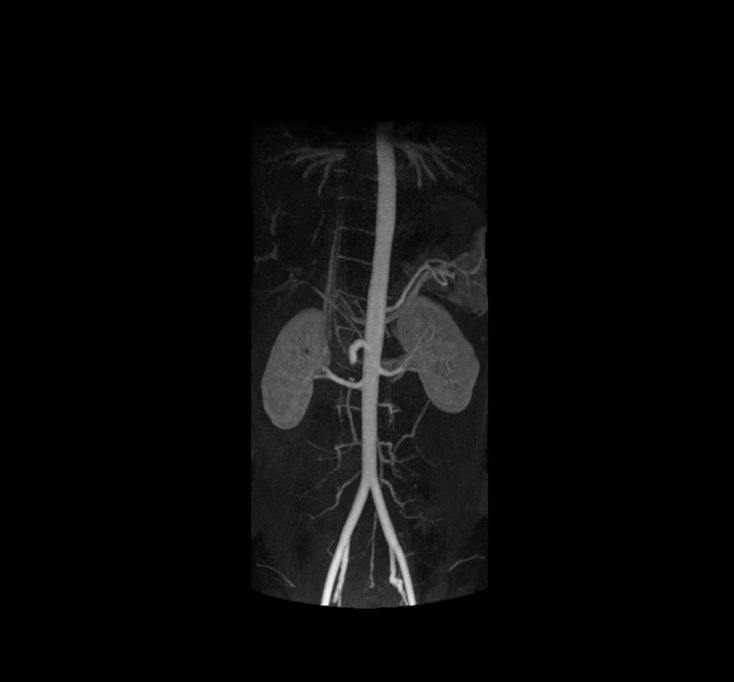

Kidney Angiography

MRI Aorta